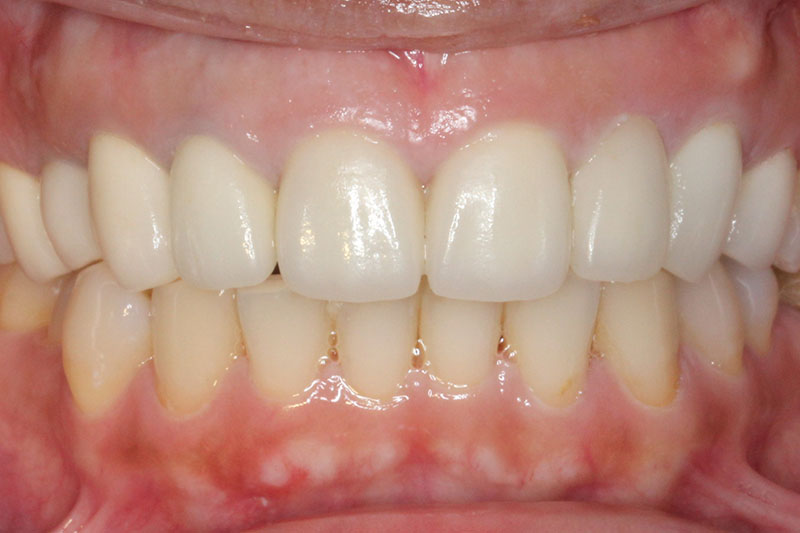

術後